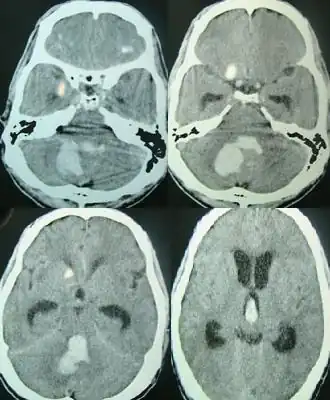

Методом выбора в диагностике внутримозгового кровоизлияния является компьютерная томография головного мозга, позволяющая не только определить наличие внутримозговой гематомы, но и оценить её локализацию, распространённость и объём, выраженность отёка мозга и степень дислокации. Для диагностики небольших гематом в стволе мозга и изоденсивных веществу головного мозга («несвежих») гематом предпочтительна магнитно-резонансная томография.

В случае невозможности проведения компьютерной томографии при отсутствии противопоказаний проводится исследование цереброспинальной жидкости, кровь в которой может свидетельствовать о кровоизлиянии в структуры задней черепной ямки или субарахноидальном кровоизлиянии. Небольшие кровоизлияния в подкорковые структуры головного мозга проявляются наличием эритроцитов в ликворе лишь через 2—3 суток[11].